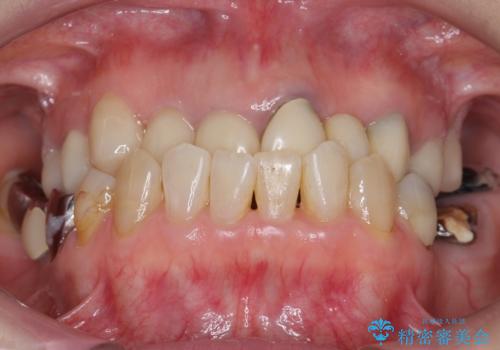

- 奥歯のブリッジの被せ物がとれてしまったとの主訴で来院された患者様です。

奥歯2本は虫歯により残っている健全歯質が少ないため、保存が難しい状態でした。

抜歯してインプラントを提案したところ、「どうしても抜きたくないので残してほしい」と強くご希望されました。

長期的な予後を保証できないことをご了承頂いた上で、歯根分割術、骨外科手術により歯の保存を試みました。